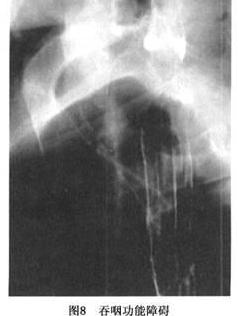

吞咽运动是下咽部、UESM、食管体部和食管下括约肌(lower esophageal sphincter muscle,LESM)松弛和收缩协同动作的结果。如果在吞咽过程中出现吞咽与其松弛不协调时,食团就难以从咽部进入食管,造成吞咽困难,即环咽肌失弛缓症,又称食管口痉挛。